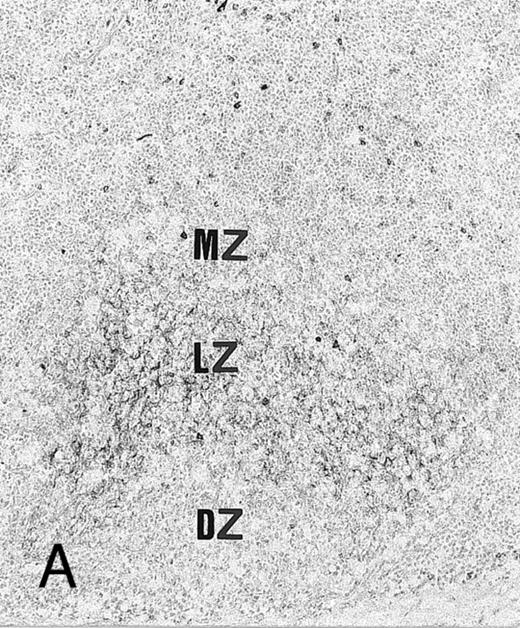

Expression of TGF-β and TGF-β receptor II in tonsillar lymphoid follicle. (A) Immunostain of TGF-β. There is the reticular and dotted positive stain in the apical and basal light zones but not the other follicular zones. MZ, mantle zone; LZ, light zone; DZ, dark zone. Counterstained with methyl green. Original magnification × 132. (B) Immunostain of TGF-βR II. There is the reticular expression in the apical light zone. OZ, outer zone; ALZ, apical light zone; BLZ, basal light zone; DZ, dark zone. Counterstained with methyl green. Original magnification × 100. (C) Immunocytochemical single staining (red color) of TGF-β on an isolated FDC. Original magnification × 1,280. (D) Double staining of TGF-β and R4/23 on the same FDC. There is a positive signal in the cytoplasm of FDC (brown). Counterstained with hematoxylin. Original magnification × 1,280. (E) In situ hybridization of TGF-β cDNA in the ALZ. Dendritic-shaped cells heavily labeled (arrows). Scattered lymphocytes are also stained (arrowheads). Uncounterstained. Original magnification × 860. (F) In situ hybridization of a TGF-βR II oligonucleotide in the ALZ. Many dendritic-shaped cells are strongly positive. Uncounterstained. Original magnification × 400.

TGF-β and TGF-β Receptor II

Immunohistochemically, the ALZ but not the other follicular zones was positive in the reticular meshwork and dotted patterns for TGF-β and TGF-βR II (Tables 3 and 4 and Fig 1A and B). Immunocytochemically, FDCs isolated with MACS were single-positive for TGF-β in their cytoplasm (Fig 1C) and double-positive for TGF-β and R4/23 (Fig 1D). Less frequently, lymphocytes isolated with MACS were positive for TGF-β (<1%). In situ hybridization using a cDNA probe for TGF-β showed the reticular and dotted patterns only in the ALZ labeling cells such as dendritic-shaped cells and lymphocytes and the scattered pattern labeling vascular walls within the whole LF (Table 5 and Fig 1E). In situ hybridization using an oligonucleotide probe for TGF-βRII showed only the reticular pattern in the ALZ labeling dendritic-shaped cells (Fig 1F). Vascular walls within the whole LF were also reacted. Follicular lymphocytes were negative. RT-PCR of samples obtained from the whole tonsillar sample as well as the GC and EGC showed a single-positive band of TGF-β (161 bp; Table 6 and Fig 2A).